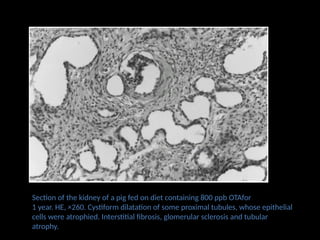

Section of the kidney of a pig fed on diet containing 800 ppb OTAfor

1 year. HE, ×260. Cystiform dilatation of some proximal tubules, whose epithelial

cells were atrophied. Interstitial fibrosis, glomerular sclerosis and tubular

atrophy.